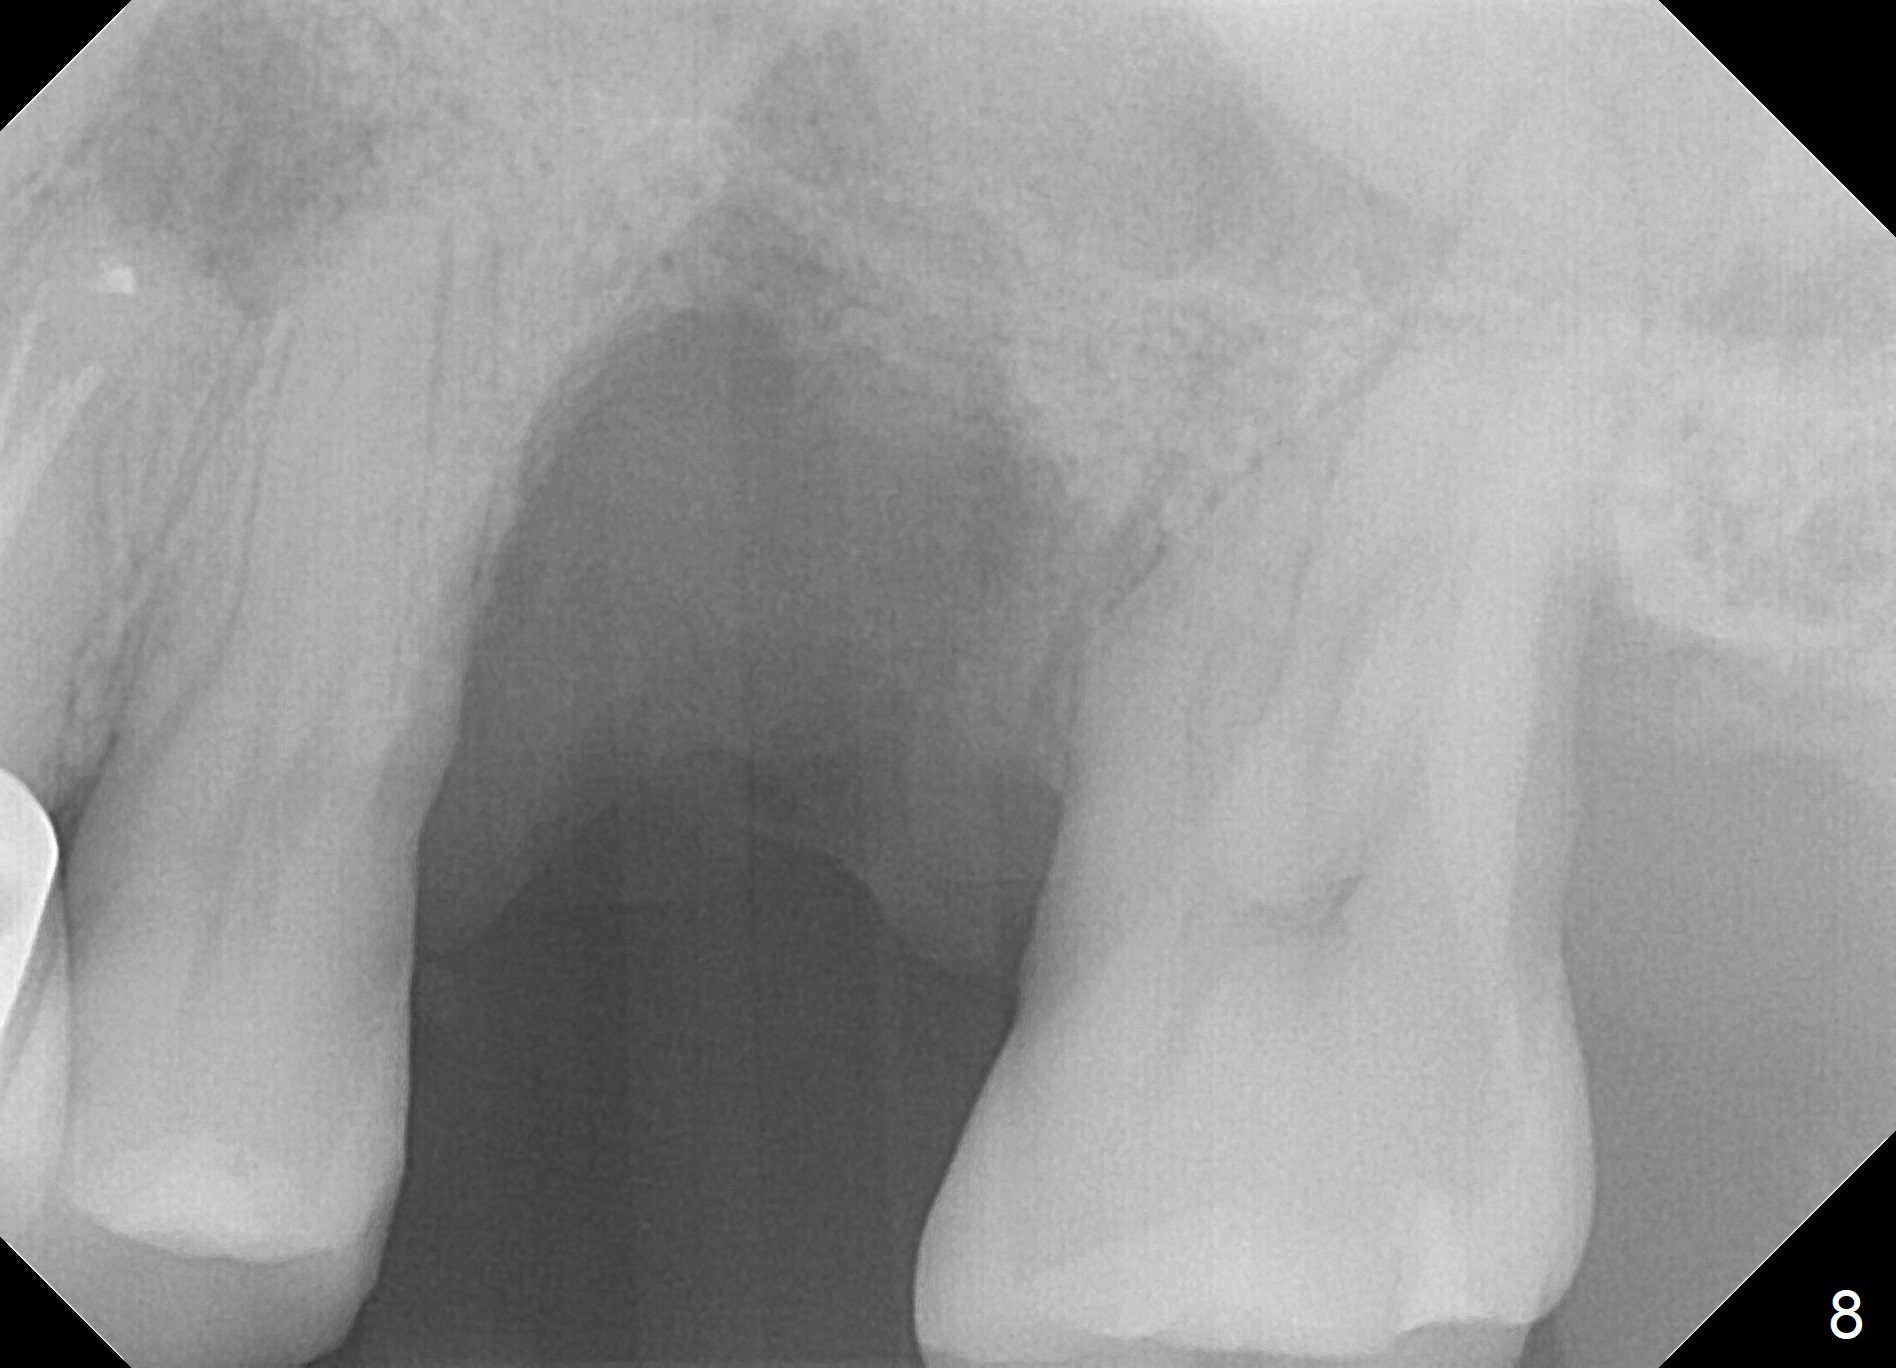

When the tooth #14 is extracted, the buccal plate is lost, while the apex of the palatal socket is perforated. The palatal slope of the septum appears to be a suitable site for osteotomy, but the depth seems to be 2 mm. After sequential osteotomy until 5.3 mm with drills, a 5.9 mm SM tap obtains stability (Fig.2). A 5.9x8 mmm implant is placed with barely sufficient stability after 1 piece of PRF membrane and VeraGraft (Fig.2-4). The implant rotates and dislodges when an abutment is being placed. Neither do 6-8x17 mm Tatum taps achieve primary stability. Socket preservation is performed, followed by periodontal dressing (Fig.5). Primary stability might have been obtained if a smaller IBS implant with fins were placed in the palatal socket. The periodontal dressing has dislodged 1 week postop; the socket appears healing (Fig.6,7). Bone graft seems to be minimal or bone density of the graft is low (Fig.8). The socket heals with a wide ridge 2 months post socket preservation, but the tooth #15 seems to be buccal (Fig.9) and mesial (Fig.10) shift. After use of Magic Split and Expanders (until 3.8 mm for 13 mm), try 5 mm dummy implant (Fig.11). If 6 mm one fails to achieve stability substantially, switch to 7 mm Tatum tapered tap provided there is enough mesiodistal space (use 8 mm implant positioner to gauze the space beforehand (preop)). Consider using Vanilla (not Vera) Graft to fill in the gap between implant and osteotomy. When primary stability is obtained, place a nonfunctional provisional to prevent further shifting (Fig.11 white outline). After osteointegration, use the provisional (reline and separator) to distalize the tooth #15.